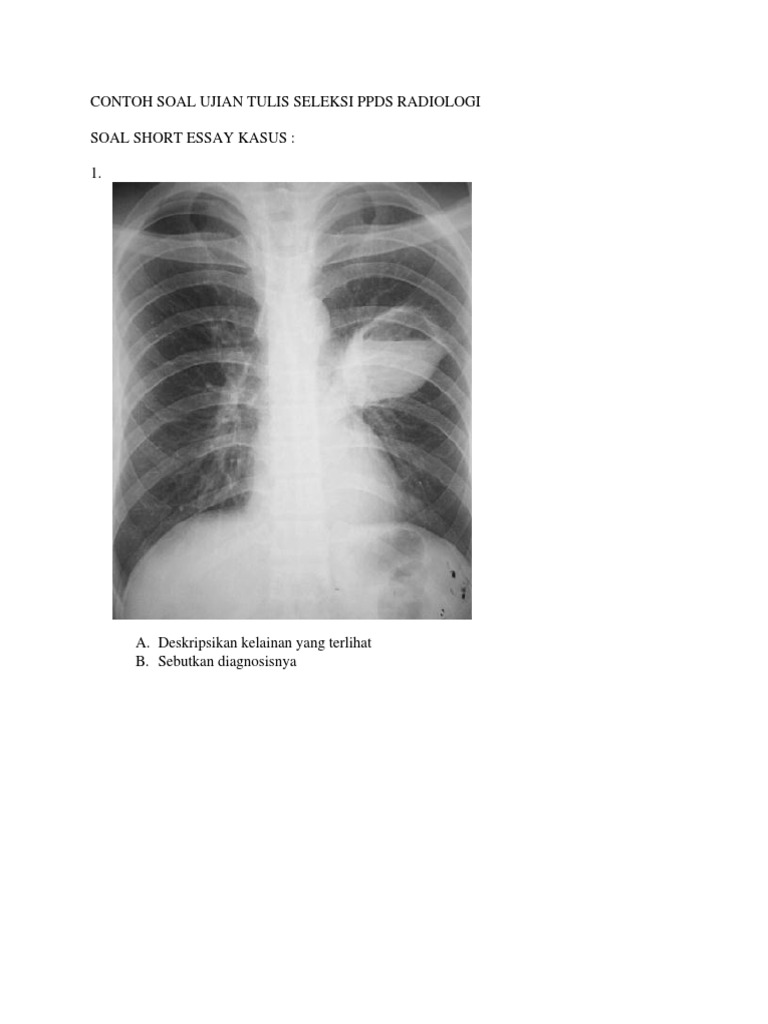

Contoh Soal Ujian Tulis Seleksi Ppds Radiologi